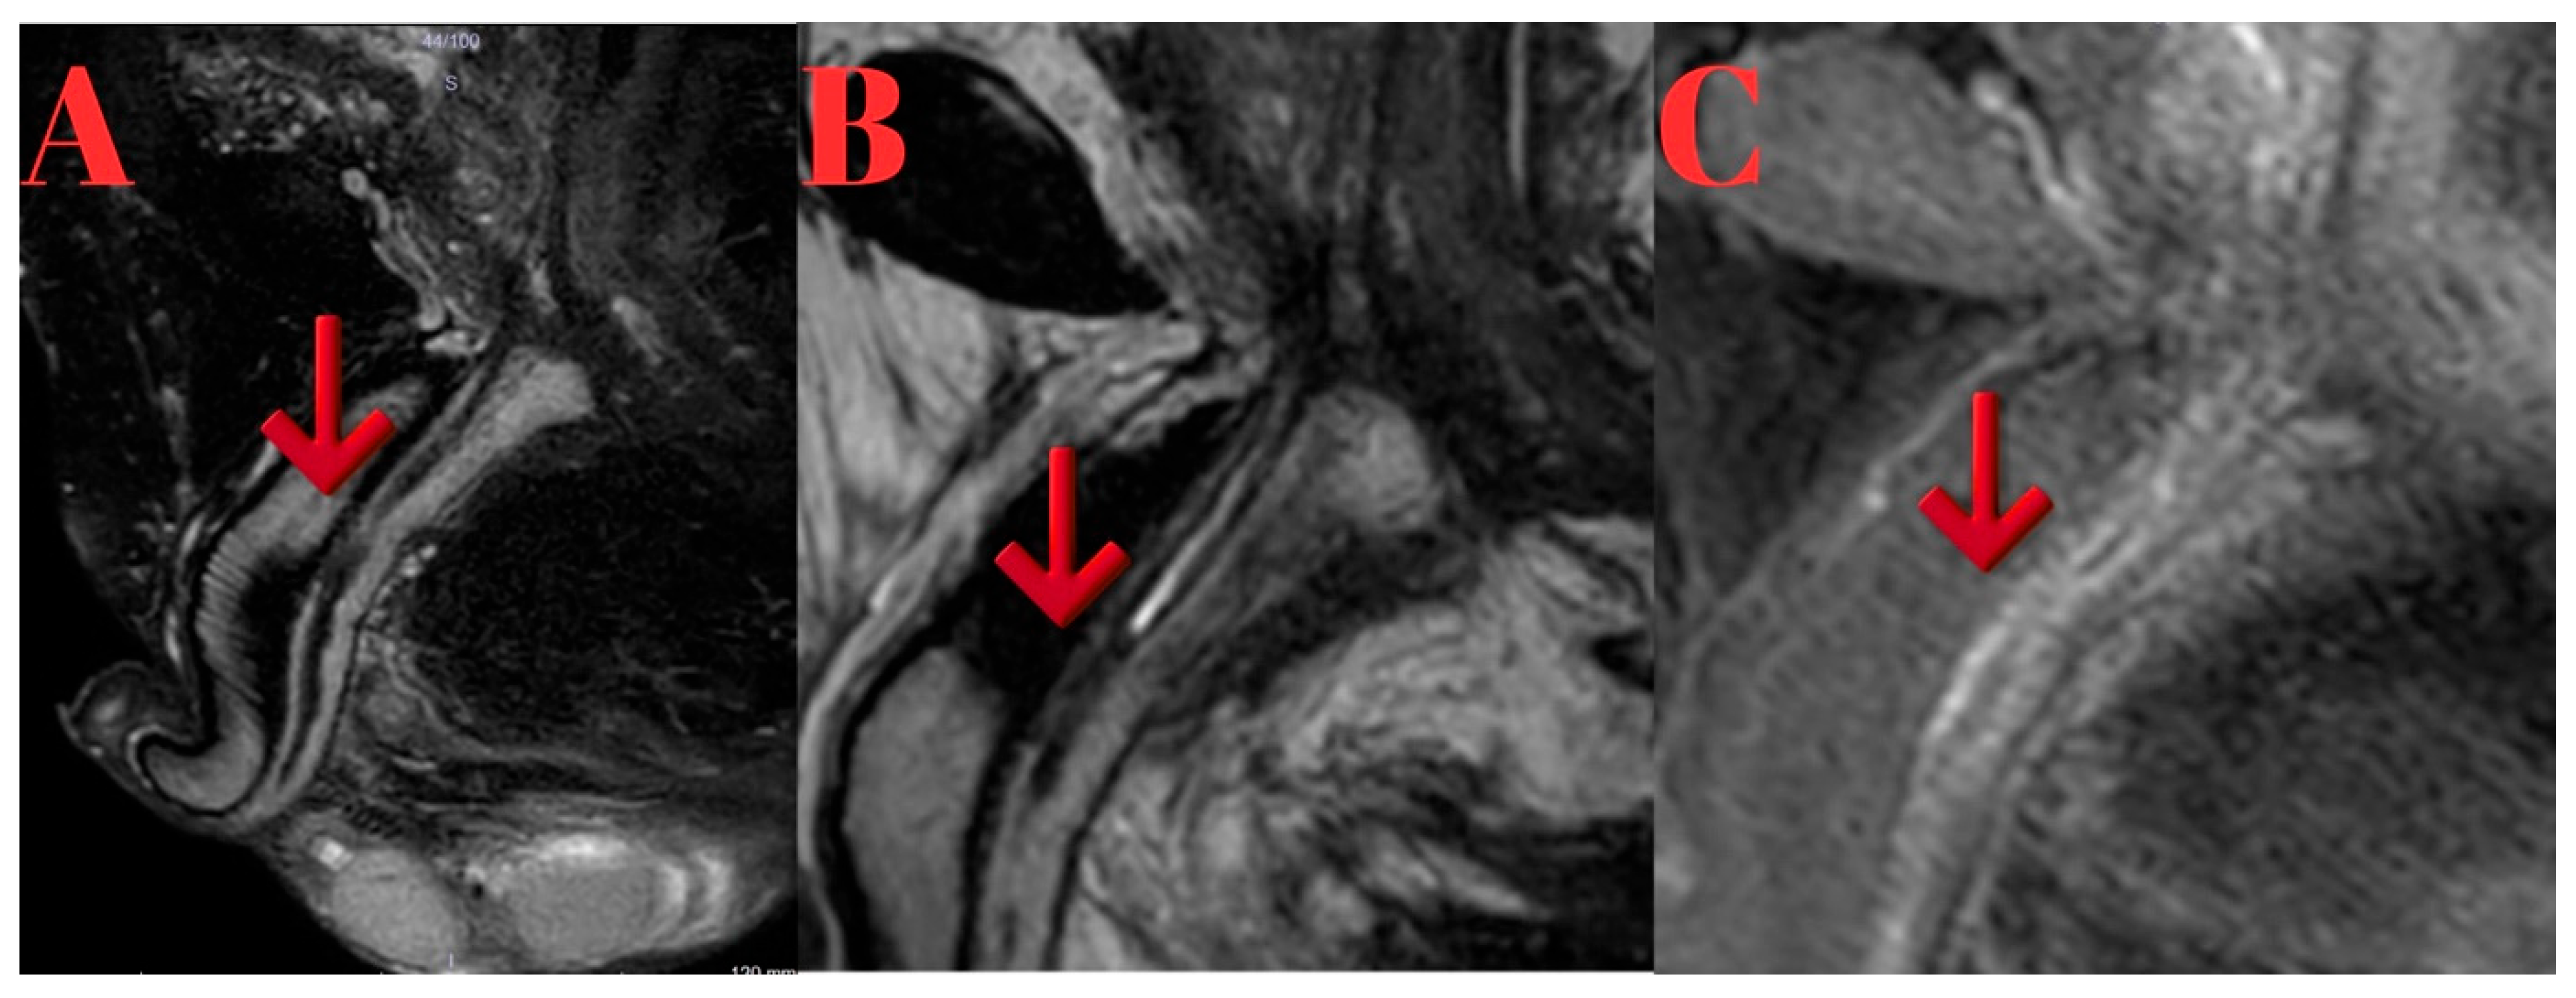

MRI findings showed lidocaine gel expanding the urethra up to the proximal bulbous urethra. T2 sagittal images demonstrated occlusion extending from the proximal bulbous urethra to the distal prostatic urethra. Post-contrast T1a sagittal imaging revealed a 1.5 cm complete obstruction in the distal prostatic urethra and a 5 mm partial stricture in the proximal bulbous urethra. Thickening of the urethral wall and enhanced inflammatory staining were noted. T1 sagittal imaging identified a 2 cm stenotic occlusive stricture area in the proximal bulbous urethra (Figure 1).

Figure 1. (A): Sagittal T2-weighted MRI showing inflammatory changes and complete obliteration extending from the proximal bulbar urethra to the distal prostatic urethra (red arrow indicating the obliterated segment). (B): Sagittal T1-weighted fat-suppressed post-contrast MRI highlighting fibrosis with contrast enhancement in the strictured segment (red arrow indicating the fibrotic lesion).